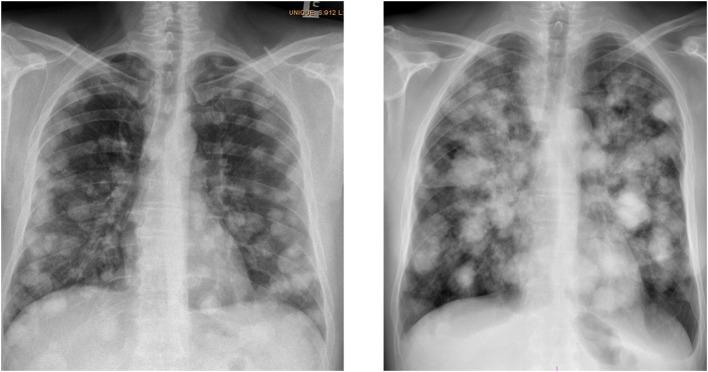

睾丸生殖细胞肿瘤(TGCTs)是年轻男性中最常见的实体瘤,也是可治愈癌症的一个范例。基于顺铂的化疗有效性确保了超过95%的患者5年生存率。然而,一些疾病非常晚期的高危患者在开始全身化疗后不久会发生与急性呼吸衰竭相关的绒毛膜癌综合征(CS),预后不良且死亡率高。CS最初被描述为TGCTs患者中具有显著高绒毛膜促性腺激素水平且伴有转移部位出血的一种综合征。肺转移灶急性出血很典型,但出血可发生于任何转移部位。绒毛膜癌细胞的特征是在CS内侵袭小血管。TGCTs患者中CS的发病率尚不明确,且在世界各地可能有所不同。迄今为止,仅有少数病例报告和小型回顾性系列报道了转移性TGCTs全身化疗与CS发生之间的关联。已知CS是由化疗导致的大量肿瘤细胞溶解和细胞因子释放引发的,肺泡出血会使其加重。这可导致连续的二重感染,化疗后中性粒细胞减少会进一步加重,引发急性呼吸窘迫综合征,进而发展为全身炎症反应,导致多器官功能衰竭和死亡。对于病情广泛的患者,一种合理有效的方法可能是缩短化疗疗程以及在全剂量化疗方案之前减少诱导化疗的剂量;然而,目前关于最佳治疗方法的数据有限。将患者转诊至三级中心并在重症监护病房环境中进行诱导化疗可能会进一步改善治疗结果。